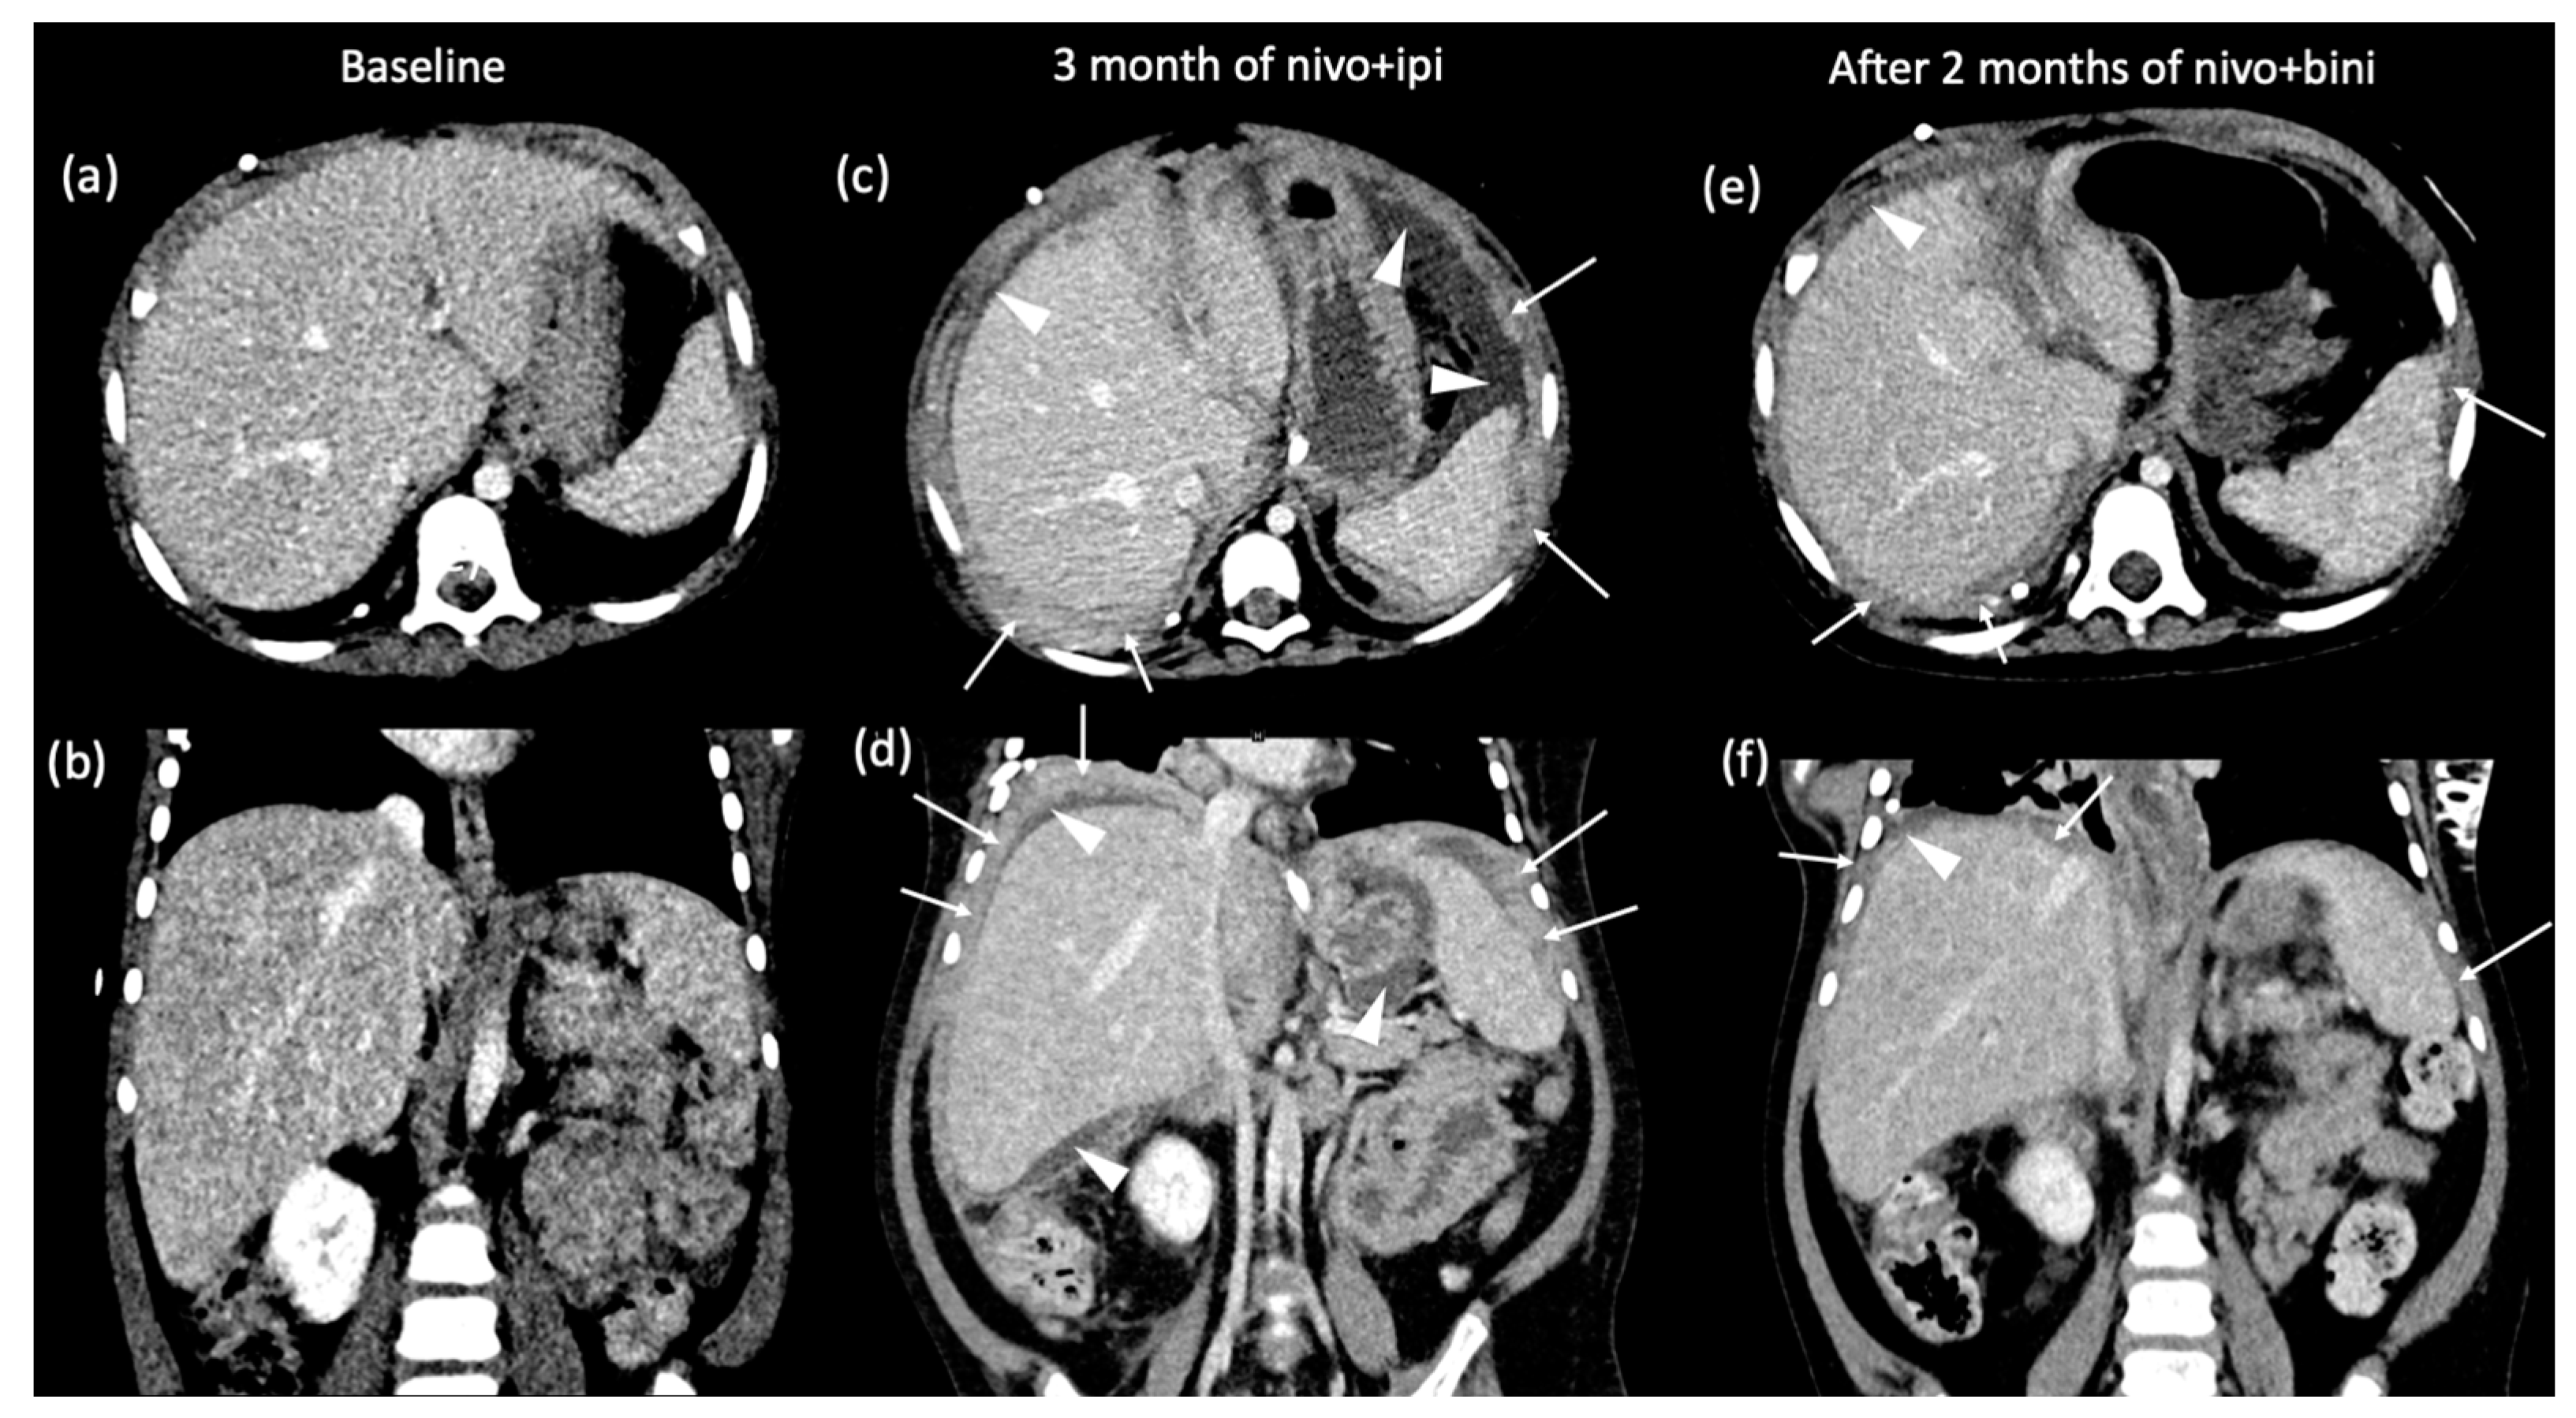

2. Case Presentation